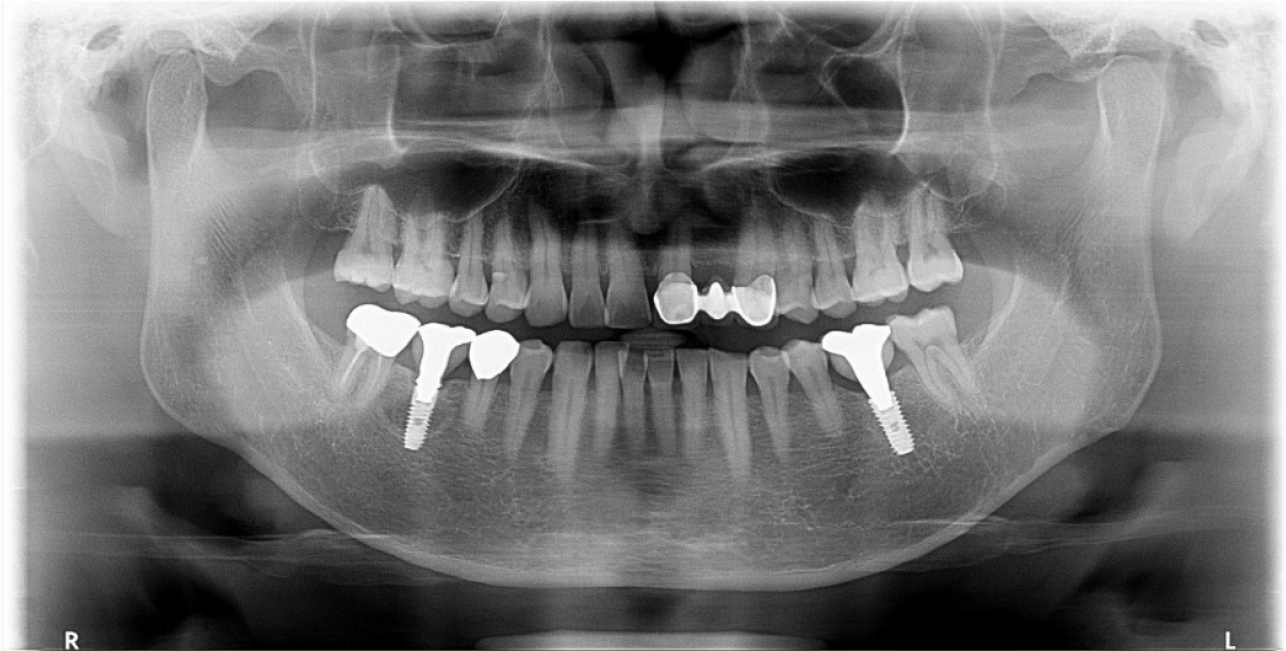

A 55-year-old man visited the clinic for implant discomfort and bleeding. The implant in the lower right 1st molar was placed three years ago at a private practice and was found to exhibit symptoms of buccal mucosal swelling and mesio-buccal deep probing pocket (Table 1). A sclerotic line on the fixture middle level was observed on panoramic and periapical radiographs (Figs. 1 and 2). There was no mobility or pus discharge but a throbbing pain during function. The probing depth was 10 mm; therefore, he was diagnosed with peri-implantitis, and we recommended implant removal. Patient hoped preservation, so regenerative therapy were preceded.

Under local anesthesia with 2% lidocaine containing 1:100,000 epinephrine (Huons, Seongnam, Korea), a buccal flap was elevated after a conventional circular incision. Most of the mid-buccal bone showed necrosis (Fig. 3). Decontamination was impossible due to the poor accessibility of the lingual part, including necrotic and inflamed portions; therefore, we decided to extract the implant using forceps.

During implant removal, the buccal remnant marginal bone was brittle and easily fell off, and the large bone defect area needed additional treatment for delayed implant placement(Fig. 4). After augmentation with a combination of 0.25 g of deproteinized bovine bone mineral (DBBM) (Bio-Oss®; Geistlich, Wolhusen, Switzerland) and 250 mg of DBBM with 10% porcine collagen (Bio-Oss collagen®; Geistlich), double layer of native bilayer collagen membrane (Bio-Gide®; Geistlich, Switzerland) was applied. The socket was sutured in an open healing state using hidden X suture (Figs. 5 and 6).9